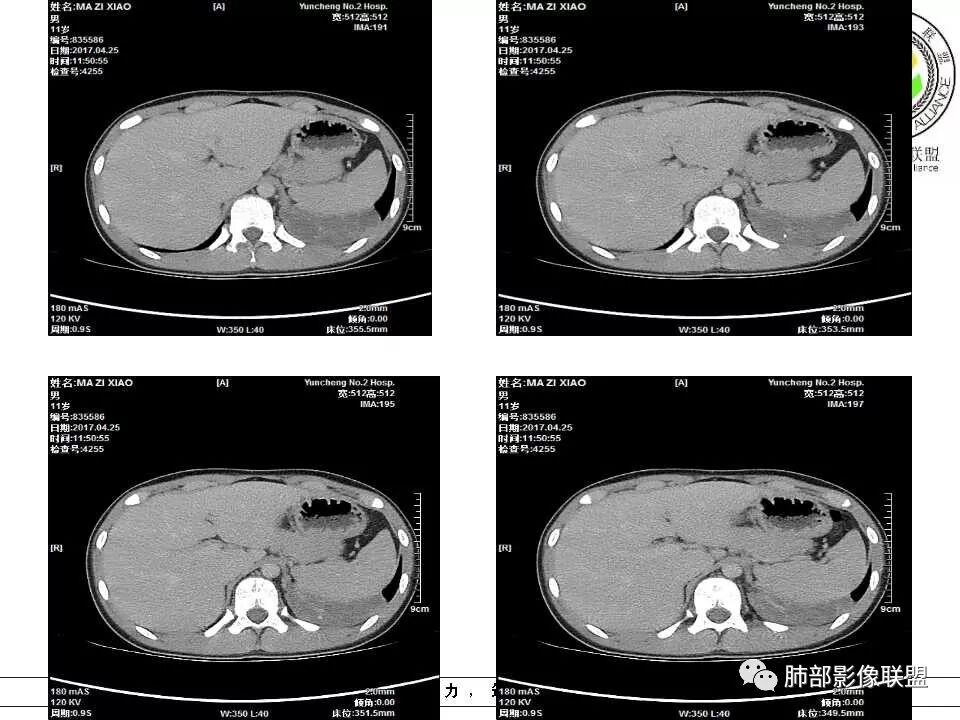

肺隔离症,供血动脉来源腹主动脉

腹主动脉供血,肺隔离症

左下肺囊状影,内有分隔,体循环供血(腹主动脉),肺静脉回流,考虑隔离症

腹主动脉供血,支持肺隔离症

左肺下叶囊性占位,腹主动脉供血,肺动脉引流,考虑肺隔离症。

左肺下叶囊性变,可见多发分隔,增强后分隔及边缘可见强化,并可见降主动脉分支进入,考虑叶外型肺隔离症

左下肺肿块,内部见多分隔,囊性密度,增强见腹主动脉分支、肺动脉供血,考虑肺隔离症,鉴别支气管囊肿

儿童,左下肺多房囊性占位,增强分隔强化,腹主动脉供血,肺隔离征。

电话随访,患者在西安某医院手术,为肺隔离症,供血两支动脉,均来自腹主动脉,引流入肺静脉。